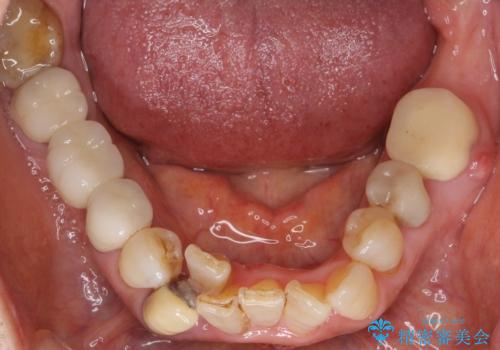

親知らずの移植 4年半経過症例 70代女性

- 親知らずの移植治療から4年半経過した患者様です。

他の歯の治療をご希望され、数年ぶりに来院して下さいました。

移植した親知らずは全く問題ないそうで、「まるで自分の歯のようです。本当にすごい技術ですね。」とおっしゃって下さいました。

歯肉の腫脹や退縮、動揺も認められませんでした。